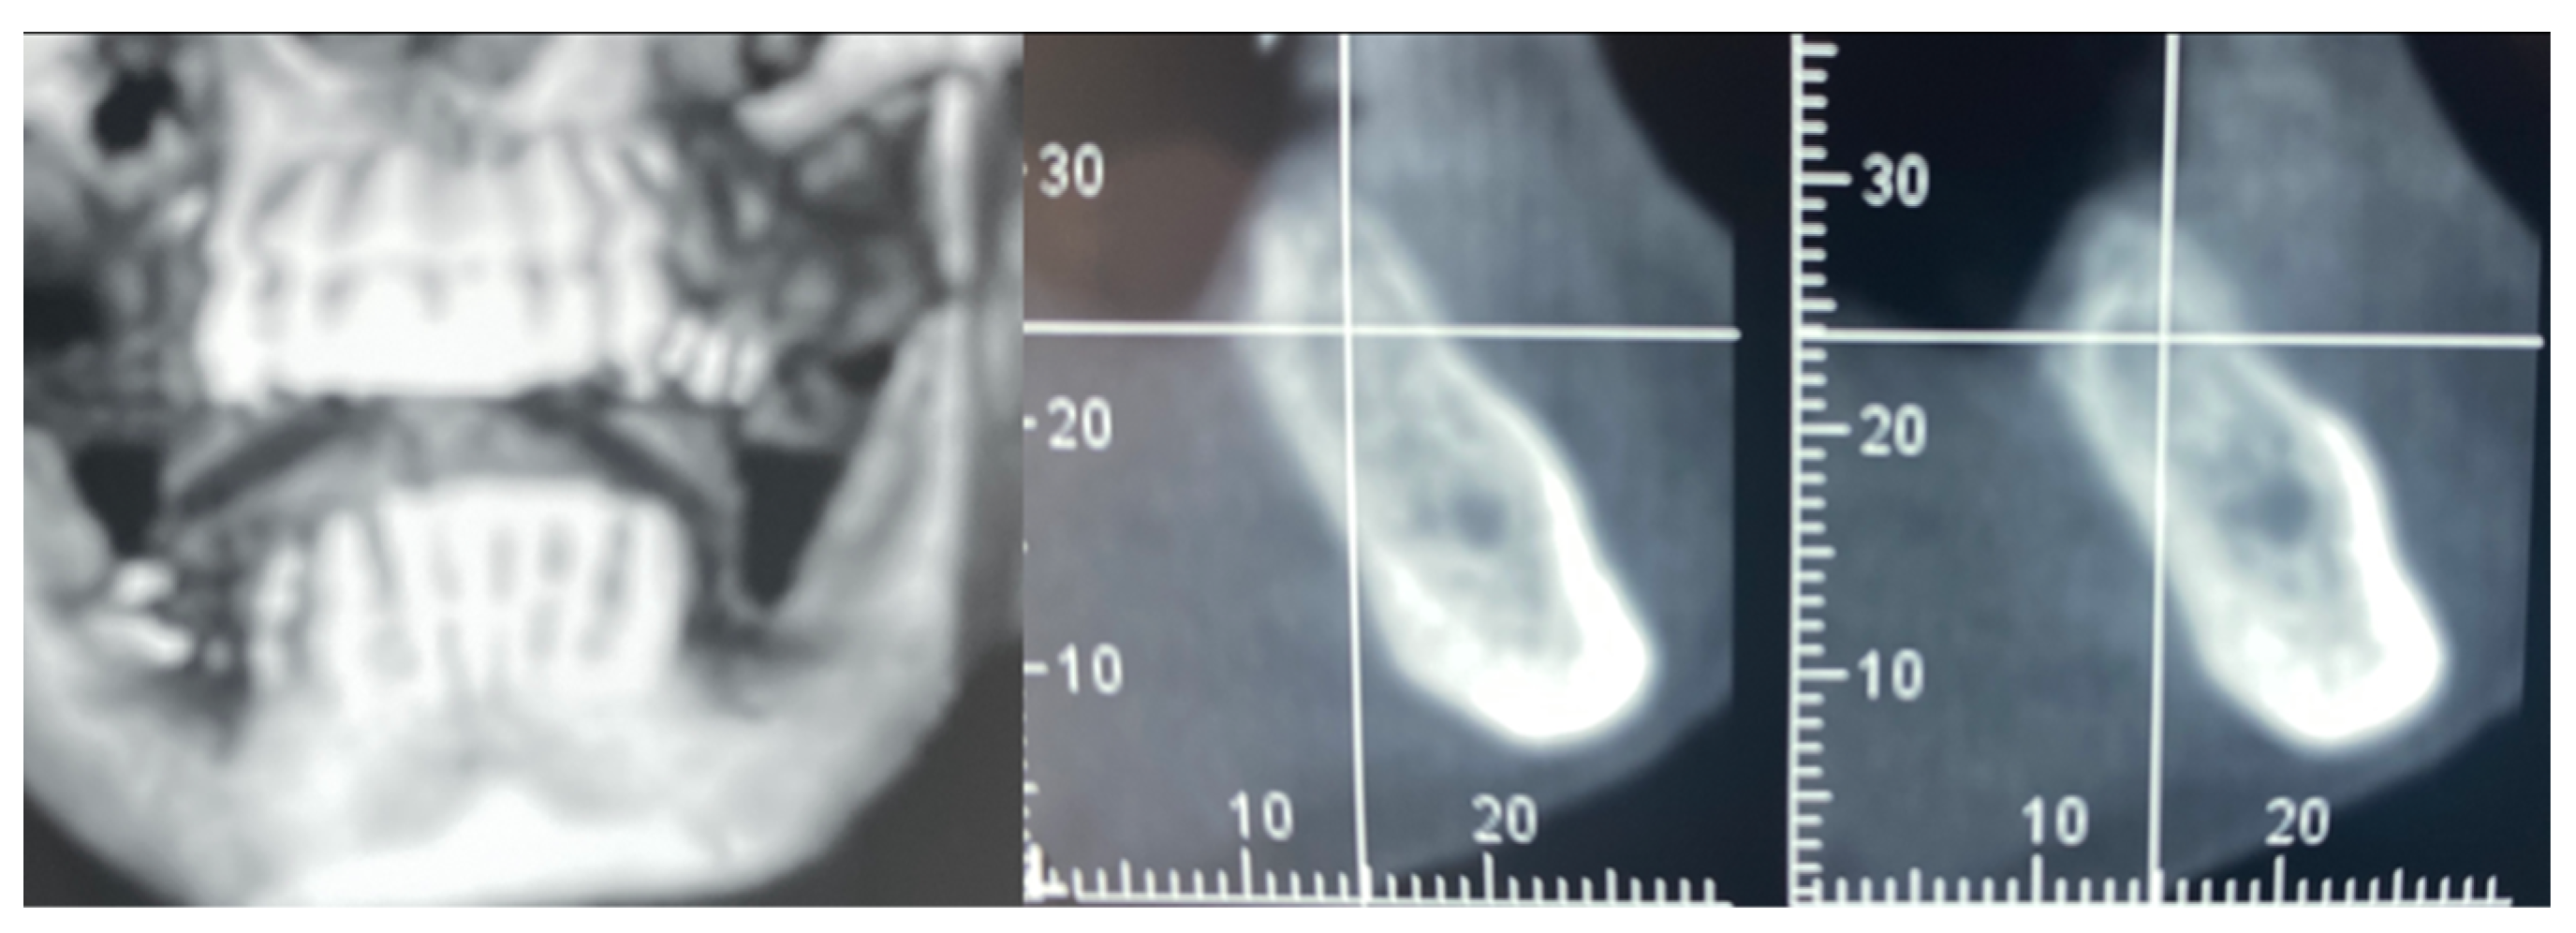

Figure 3.

CBCT at baseline: (a) volumetric reconstruction of the edentulous area; (b) cross-section of the area.

In this case of important bone augmentation, a healing period of 8 months was observed. Indeed, biomaterials, such as FCS, require a longer time than autogenous bone. No complications were experienced during the follow-up. At the end of the healing period, CBCT was performed to plan the implants’ insertion (Figure 8). It was pleasant to observe that the GBR provided the desired volume augmentation for the ridge. The CBCT showed a horizontal and vertical ridge augmentation of 8 mm and 8 mm, respectively.

Figure 8.